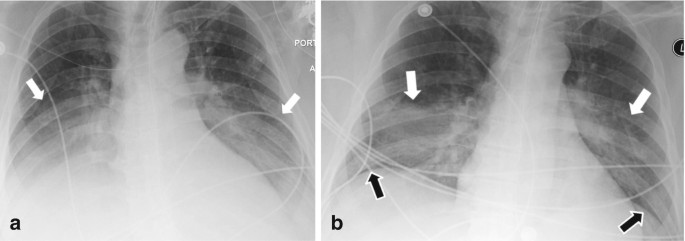

Recognition of pleural effusion on supine radiographs: how much fluid is required?

Imaging Subpulmonic Effusions - wikiRadiography

Pleural effusion is not always visible as a meniscus ... | GrepMed